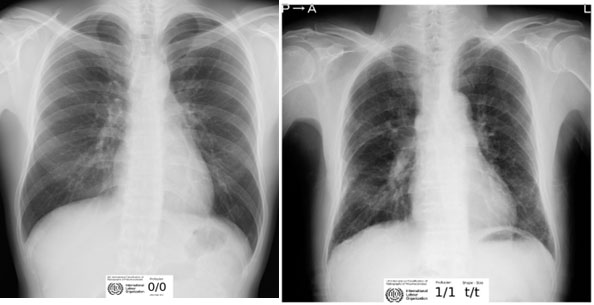

Radiografía de tórax con técnica OIT: La radiografía de tórax con técnica OIT es una herramienta clave en el diagnóstico de la asbestosis. Puede mostrar la presencia de opacidades pulmonares características (opacidades irregulares), que son indicativos de la enfermedad.

En resumen, se considera en estadio temprano con una Radiografía de Tórax con técnica OIT (Organización Internacional del Trabajo), en categoría 1 de la Clasificación OIT, interpretada (leída) a lo menos por dos lectores certificado en esta técnica, e informadas en profusión 1/0 o mayor, que muestre opacidades irregulares. 35 Se debe realizar tomografía computarizada de tórax de alta resolución sin contraste (TCAR), cuando la lectura de Radiografía de Tórax con técnica OIT se defina en profusiones 1/0 y 1/1, que muestre opacidades irregulares. Historia Ocupacional (HO) para fibra de amianto: la valoración exhaustiva del sitio donde el trabajador está expuesto a fibras de amianto por el profesional higienista es fundamental, quien proveerá datos sobre tipo/cantidad de fibras de amianto, tiempo/ calidad de la protección colectiva y personal, altura geográfica y tiempo de exposición en días/semanas/años.

Obligatoria: Radiografía de tórax con técnica OIT. 35 Informe de lectura de la radiografía de tórax con técnica OIT, realizada por lector acreditado.

Complementaria: Tomografía computadorizada de tórax de alta resolución. 36 (TCAR), sin contraste: en caso de lectura de radiografía de tórax con técnica OIT que muestre opacidades irregulares de predominio, en bases pulmonares con profusión 1/0 y 1/1. Además, es una herramienta fundamental para la realización de diagnóstico diferencial (Figura 2).